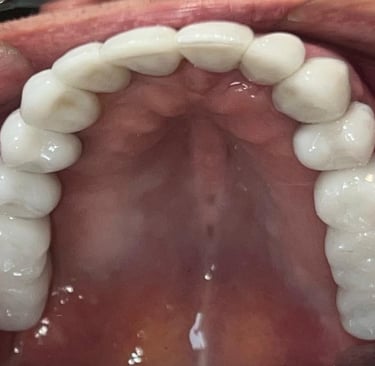

Aspecto Clínico Final - Fotografias originais — nenhuma contém retoques — A cor dos dentes é escolhida de acordo com o gosto e a preferência estética de cada paciente.

Coroas em Dissilicato de Lítio

Todos os caso a seguir estão associadas a clareamento dentário

Caso que demonstra a vantagem da integração de diversas áreas da odontologia, unindo cirurgia, periodontia, prótese e estética para alcançar resultados funcionais e harmônicos.